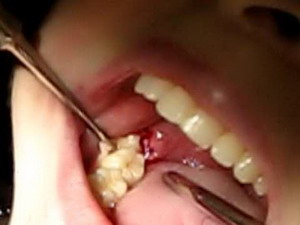

Bộ dụng cụ nhổ răng

Việc nhổ bỏ các chân răng thường không phức tạp như nhiều người thường nghĩ, bác sĩ sẽ khám xem có cần thiết phải chụp X-quang, có thể cần thực hiện một số xét nghiệm trước khi nhổ. Hiện nay, với sự phát triển của nhiều loại thuốc tê rất hiệu quả, sau khi gây tê sẽ không có cảm giác đau tại vùng răng cần nhổ, bác sĩ sẽ sử dụng các dụng cụ thích hợp để nhổ bỏ chân răng nhiễm trùng, nạo sạch các mô bệnh lý ở vùng quanh chóp.